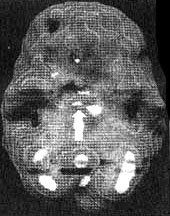

Мозг Нэнси — последствия двух инсультов

Трехмерное изображение поверхности, вид сверху

Трехмерное изображение поверхности, вид справа

2. SPECT позволяет дать точную оценку состояния пациента, позволяющую предотвратить, заболевание в будущем. Нэнси, 59 лет, страдала от тяжелой депрессии, не поддававшейся лечению. Поступила в психиатрическую лечебницу, где ей было проведено исследование SРЕСТ. Каково же было мое удивление, когда оказалось, что в прошлом, при полном отсутствии соответствующих симптомов, она перенесла два обширных инсульта. Таким образом, стало понятно, что вызвало эту депрессию, не поддававшуюся обычному лечению. У 60 % пациентов, перенесших кровоизлияние во фронтальных долях, через год развивается тяжелая депрессия. Получив результаты SPECT, я немедленно проконсультировался с неврологом, который постарался определить причины инсультов, к которым нередко приводят, скажем, бляшки в сонных артериях или сердечная аритмия. Он пришел к выводу, что причиной инсультов у Нэнси стали тромбы, и назначил ей препараты, снижающие вязкость крови, чтобы предотвратить развитие новых инсультов.